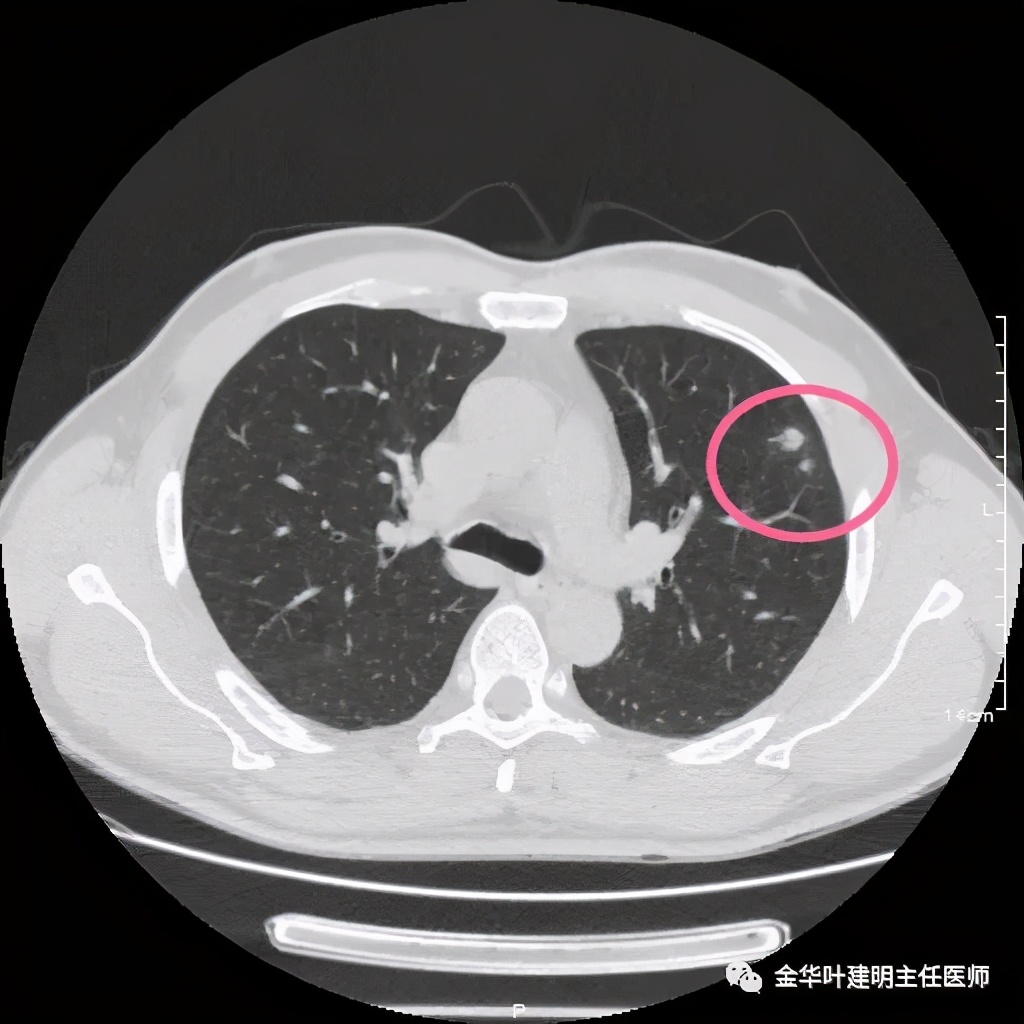

患者为48岁男性,检查发现左肺上叶实性结节,临床没有炎症表现,肿瘤指标不高,没有查过结核及隐球菌荚膜抗原试验或G试验、M试验等。我们先来看其前一个月时的平扫影像:

上图示有血管征,与病灶关系较密切

上图示血管与病灶临近,但没有被病灶牵拉从而进入病灶

上图血管有分支进入病灶

上图示纵隔窗,没有钙化

我们见左上实性病灶,主病灶旁有卫星灶,有血管进入,但也有贴边走行,边缘略显模糊,膨胀感与细毛刺不明显,收缩力也不明显。下面是其靶扫描的片子: